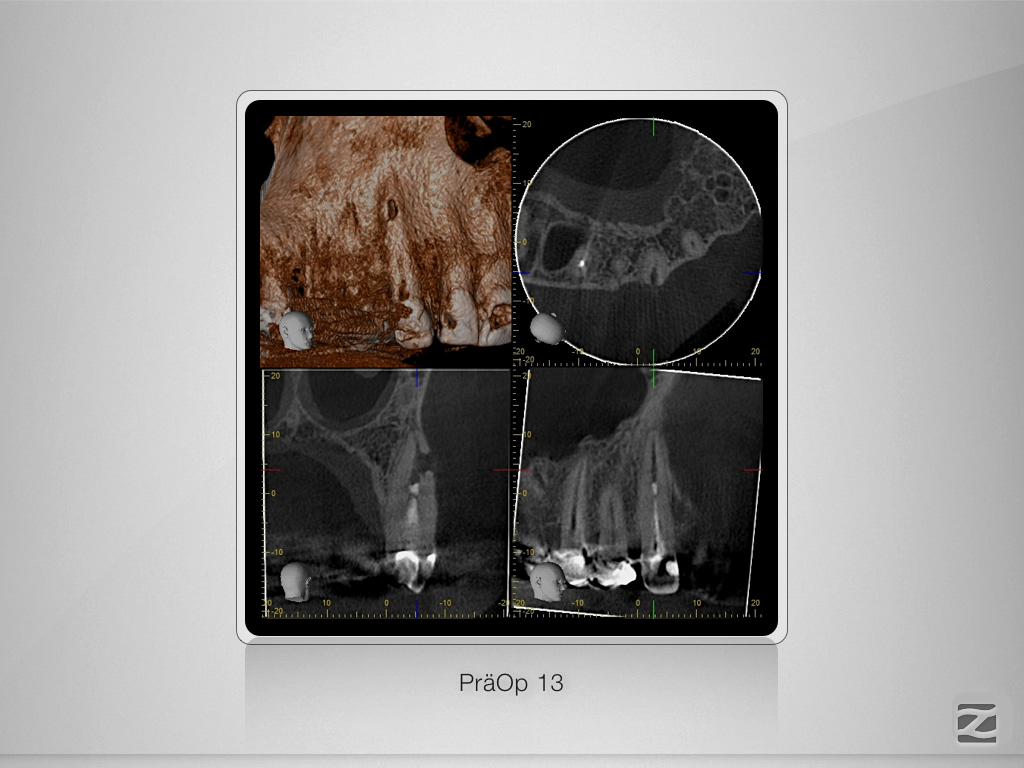

13d-002 Veröffentlicht 26. Januar 2017 am 1024 × 768 in 2-Jahres-Recall einer perforierenden Resorption